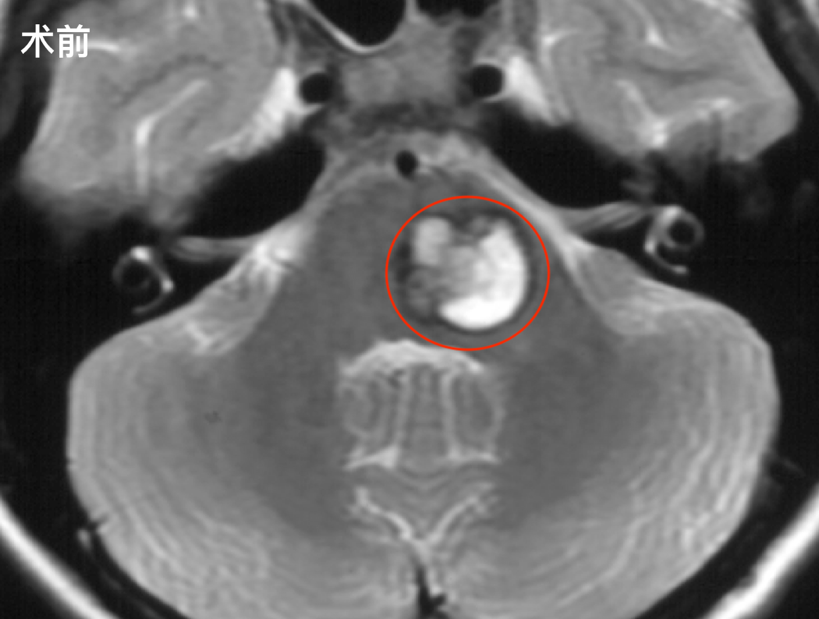

病情初期,小枝仅表现为视物重影,自认为学习压力所致,使用眼药水后未见改善。随后出现黑板字迹模糊、四肢无力、易跌倒等症状。意识到情况异常后,她立即告知父母,就医检查确诊脑干占位性病变,考虑脑干海绵状血管瘤。

手术由巴教授主刀,采取乙状窦后入路开颅方式,在显微镜下成功全切肿瘤,术中全程实施电生理监测。手术过程顺利,经直尺测量脑干病变切除切口仅3cm,脑干表面切口仅0.5cm,证明巴教授在极小操作空间内实现肿瘤全切的高超技术。